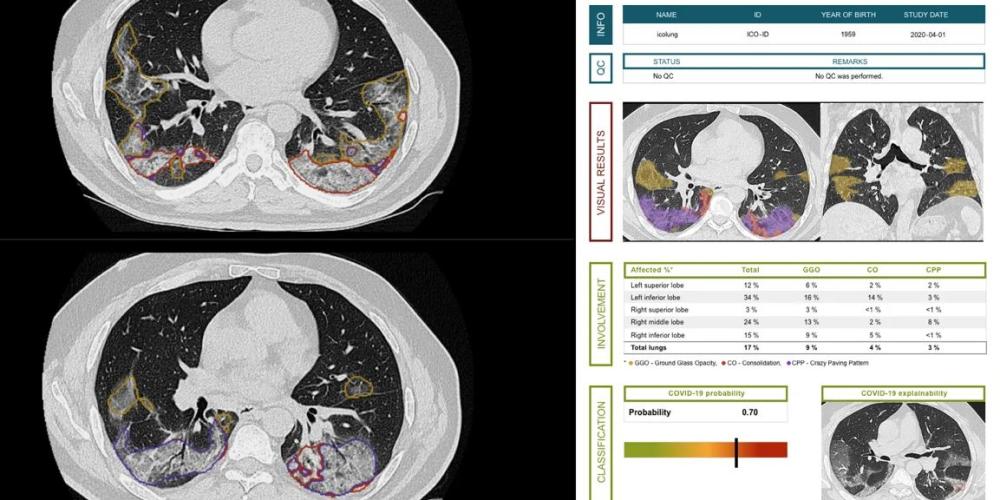

Professor Jef Vandemeulebroucke of ETRO: “What started as a local project is now being rolled out in 800 hospitals in Europe and supported by excellent research centres all over Europe. With icolung, we can detect COVID-19 patients at an early stage and quantify the extent of lung lesions. Meanwhile, we are further improving the AI software to identify lung damage as COVID-19 even more quickly, and to determine the further care path of the patient faster and better through prognostic models.”

icolung was certified in April and is currently being used by over 75 hospitals worldwide and has analysed over 35,000 lung CT scans. The icovid project now builds on the development of icolung and is committed to scaling up, thanks to the commitment of renowned research institutes such as King’s College London, Universitätsklinikum Heidelberg, University of Oxford, Maastricht University and the University and Centre Hospitalier Universitaire of Liège. The partners will also collaborate with The Medical Cloud Company to incorporate other clinical information into the models in addition to CT images.

The icovid project was launched in March 2020 as a Belgian pro deo initiative. icometrix, which specialises in AI solutions for medical images, partnered with UZ Brussel, KU Leuven, VUB and imec to investigate how to deploy lung scans in the COVID pandemic and what AI software would be needed to do so. The AI tool icolung was born.

Prof Johan de Mey, VUB-UZ Brussel: “At the time, there was insufficient testing capacity to quickly test all patients. With icolung, we wanted to use lung scans as a triage tool. By using CT and with the help of the AI analyses, we were able to trace patients with suspicious lung lesions and have them tested as a priority. During the busiest periods, everyone who entered the UZ Brussel as a patient was scanned, also as a means of preventing COVID-19 outbreaks in the hospital.”